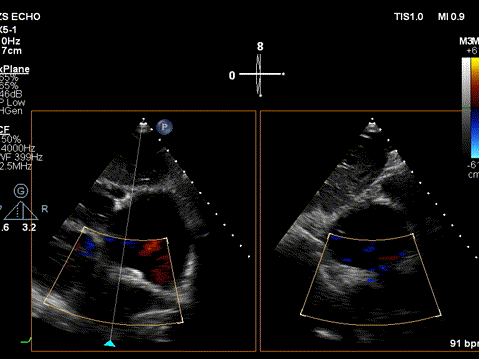

图片

术前心超

房间隔没有血流

术后心超

心房间可见分流束

术后超声评估:

1. 房间隔分流器植入术后;

2. PASP 61mmHg,重度三尖瓣反流,继发性右房室增大,右室壁增厚伴收缩活动减弱;

3.轻度二尖瓣反流;